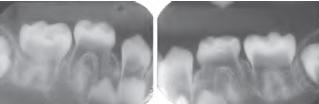

Simple Bone Cyst 單純性骨囊腫 |

空()或液體骨腔 | 肱骨、 股骨近端、 下顎後牙、 下顎聯合區 | 年輕人 | 少疼痛、皮膚感覺異常 |

不須積極治療,復發率低 (例外: cementoosseous dysplasia) |

侵犯牙根之間區域,不影響鄰牙,近遠心擴張 ![]() |